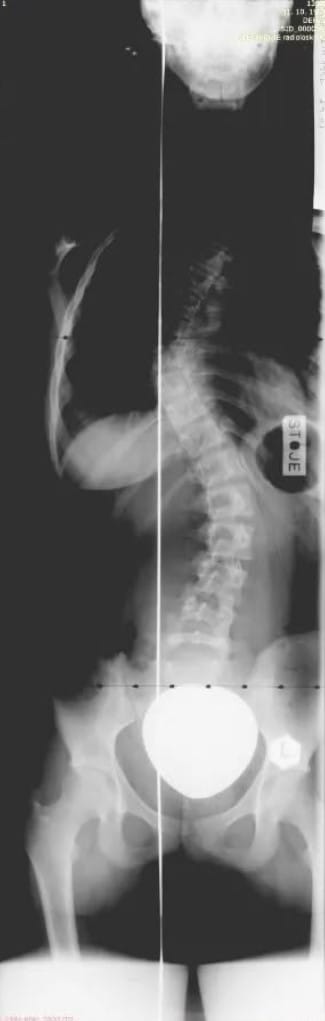

Okoli vseh teh dogodkov smo tretjič slikali hrbtenico.

Moja hrbtenica leta 2007

Katastrofalen izid. 56° v prsnem košu in 45° v ledvenem. Jezni pogledi ortopedov in sester, da če smo pametni, bom šla na operacijo in naj se nehamo hecati…

Šok. Zakaj so mi vsi terapevti govorili, da je ok, da je skolioza čisto majhna, slika pa je bila katastrofalna. Ogromno jeze sem imela takrat v sebi, sploh, ker nihče ni ničesar ukrenil, nobenih odgovorov nisem dobila zakaj eni pravijo tako in drugi tako… In takrat sem nehala delati. Nehala obiskovati terapije, nehala telovaditi, ker sem imela vsega dovolj.